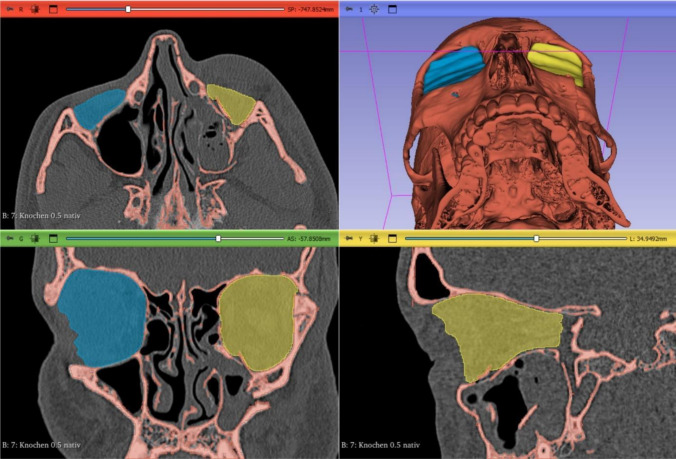

目的:眶壁重建是CMF重建手术中的一个挑战,因为眶壁解剖结构脆弱,且治疗效率低下可能导致眶壁功能受损。生物材料在重建手术中的应用已经彻底改变了这一领域的治疗方法。超高分子量聚乙烯(UHMWPE)由于其生物相容性、机械性能和多功能性而显示出很好的应用前景。本文首次报道了超高分子量聚乙烯(UHMWPE)在眼眶骨折重建中的临床应用。方法:在一项包括50例眶底重建患者的多中心前瞻性研究中,使用超高分子量聚乙烯(UHMWPE)植入物重建骨折后的眶体积。46例患者行术前术后三维x线摄影和眶体积分割。结果:在整个队列中观察到术后受影响的眼眶体积明显减少(p结论:UHMWPE (marPOR)种植体眶壁重建是一种可靠的方法,可以恢复创伤患者足够的眼眶体积,以恢复功能和美观。

Methods: In a multicentre prospective study consisting of 50 patients undergoing orbital floor reconstruction, UHMWPE implants were used to reconstruct the orbital volume after fracture. 46 Patients underwent preoperative and postoperative 3D radiography and orbital volume segmentation.